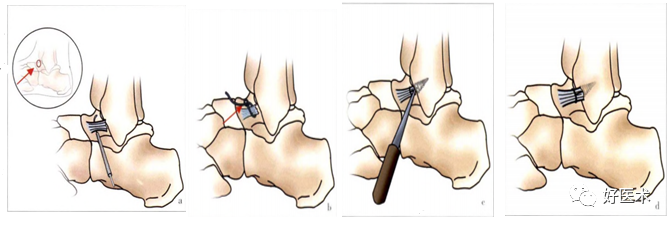

图片

上图为全镜下无结锚钉技术修复距腓前韧带治疗慢性踝关节外侧不稳手术操作示意图。a使用过线器穿刺韧带残端并引入碳纤钢丝,红箭头示切口;b用碳纤钢丝引入套环线并捆扎韧带残端(箭头示);c用无结锚钉穿入尾线并将锚钉置入足印区,恢复张力、固定韧带残端;d韧带修复后示意图,镜下检查韧带止点修复满意,韧带张力适中(来自参考文献9)